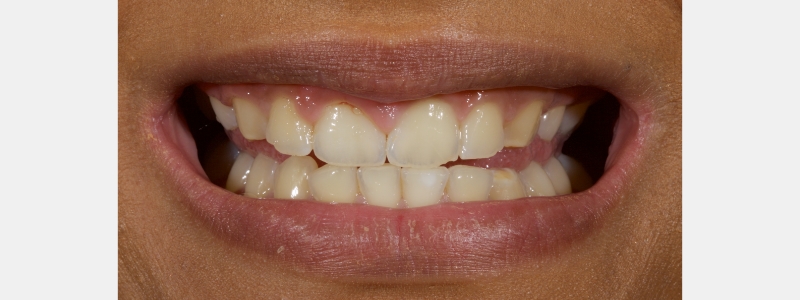

A diagnosis of altered passive eruption (APE) alongside tooth surface loss (TSL) secondary to parafunction was made for a referred female patient in her early 20s who complained of having“short, fat, baby teeth.” Due to her age, she was treated with a simple gingivectomy (after bone sounding), nightguard vital bleaching (NGVB), and additive edge bonding.

The worn incisal edges were restored with edge bonding, a new technique for restoring worn dentition. This should be regarded as a multiple Class IV restoration.